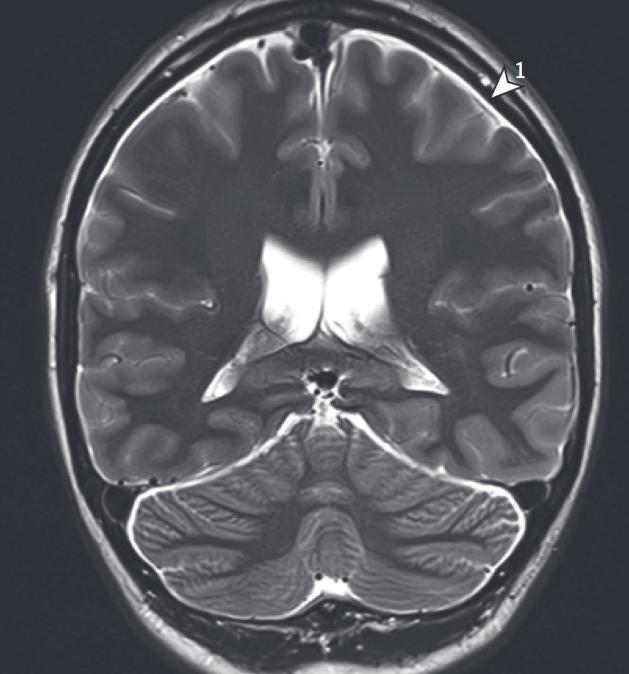

SIH Score

1) Subdurale Flüssigkeitsansammlung. Dobrocky T. et al. 2019. JAMA Neurology.